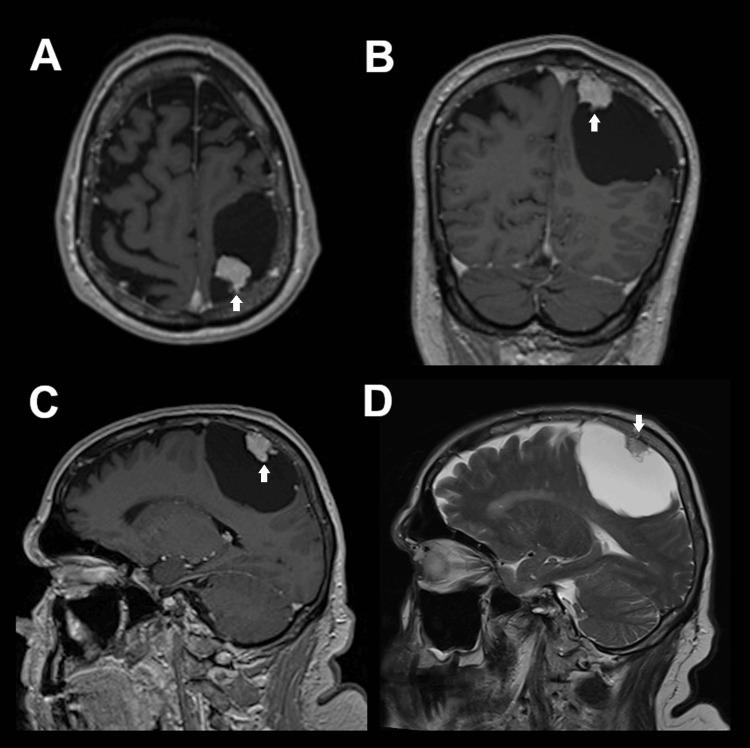

脑膜瘤是最常见的颅内良性肿瘤。其中,囊性血管母细胞型脑膜瘤是非常罕见的类型,术前与其他肿瘤进行鉴别具有挑战性。我们报告1例矢状窦旁血管母细胞型脑膜瘤病例,其伴有一个大的相关囊肿,术前影像学表现类似血管母细胞瘤。该病例接受了手术治疗。我们还进行了文献回顾,共检索到10篇英文文献,描述了一些类似的囊性血管母细胞型脑膜瘤病例。结论:本报告描述了1例罕见的囊性血管母细胞型脑膜瘤病例,其术前影像学表现独特,为该领域稀少的文献增添了内容。手术最终是这些患者进行诊断和减轻脑实质压迫的关键方法。

Parasagittal cystic meningioma mimicking hemangioblastoma: A case report.酷似血管母细胞瘤的矢状旁囊性脑膜瘤:一例报告